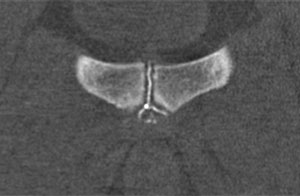

Ergänzend ist es oftmals sinnvoll eine Symphysographie durchzuführen. Bei dieser röntgenologisch oder CT-gestützten Untersuchung lässt sich das Ausmaß des Cleft-Syndroms und seine genaue Lokalisation darstellen. Die Cleft-Syndrome werden abhängig vom Schweregrad der Verletzung und der beteiligten anatomischen Strukturen in PLACT 1 – PLACT 6 eingeteilt. An Hand des im MRT sichtbaren Schweregrades der Verletzung kann die Therapie mit dem/der Patienten/in geplant werden.